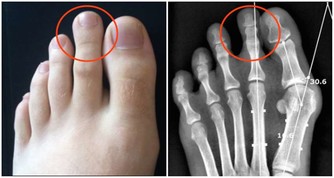

白內障

白內障是指晶狀體因各種原因發生渾濁,由透明變成不透明,阻礙了光線進入眼內所致。主要症狀是無感覺的進行性視力減退和視物模糊,若逐漸加重會導致失明。注意預防代謝性和並發性白內障。如患糖尿病就易誘發白內障,應注意預防。